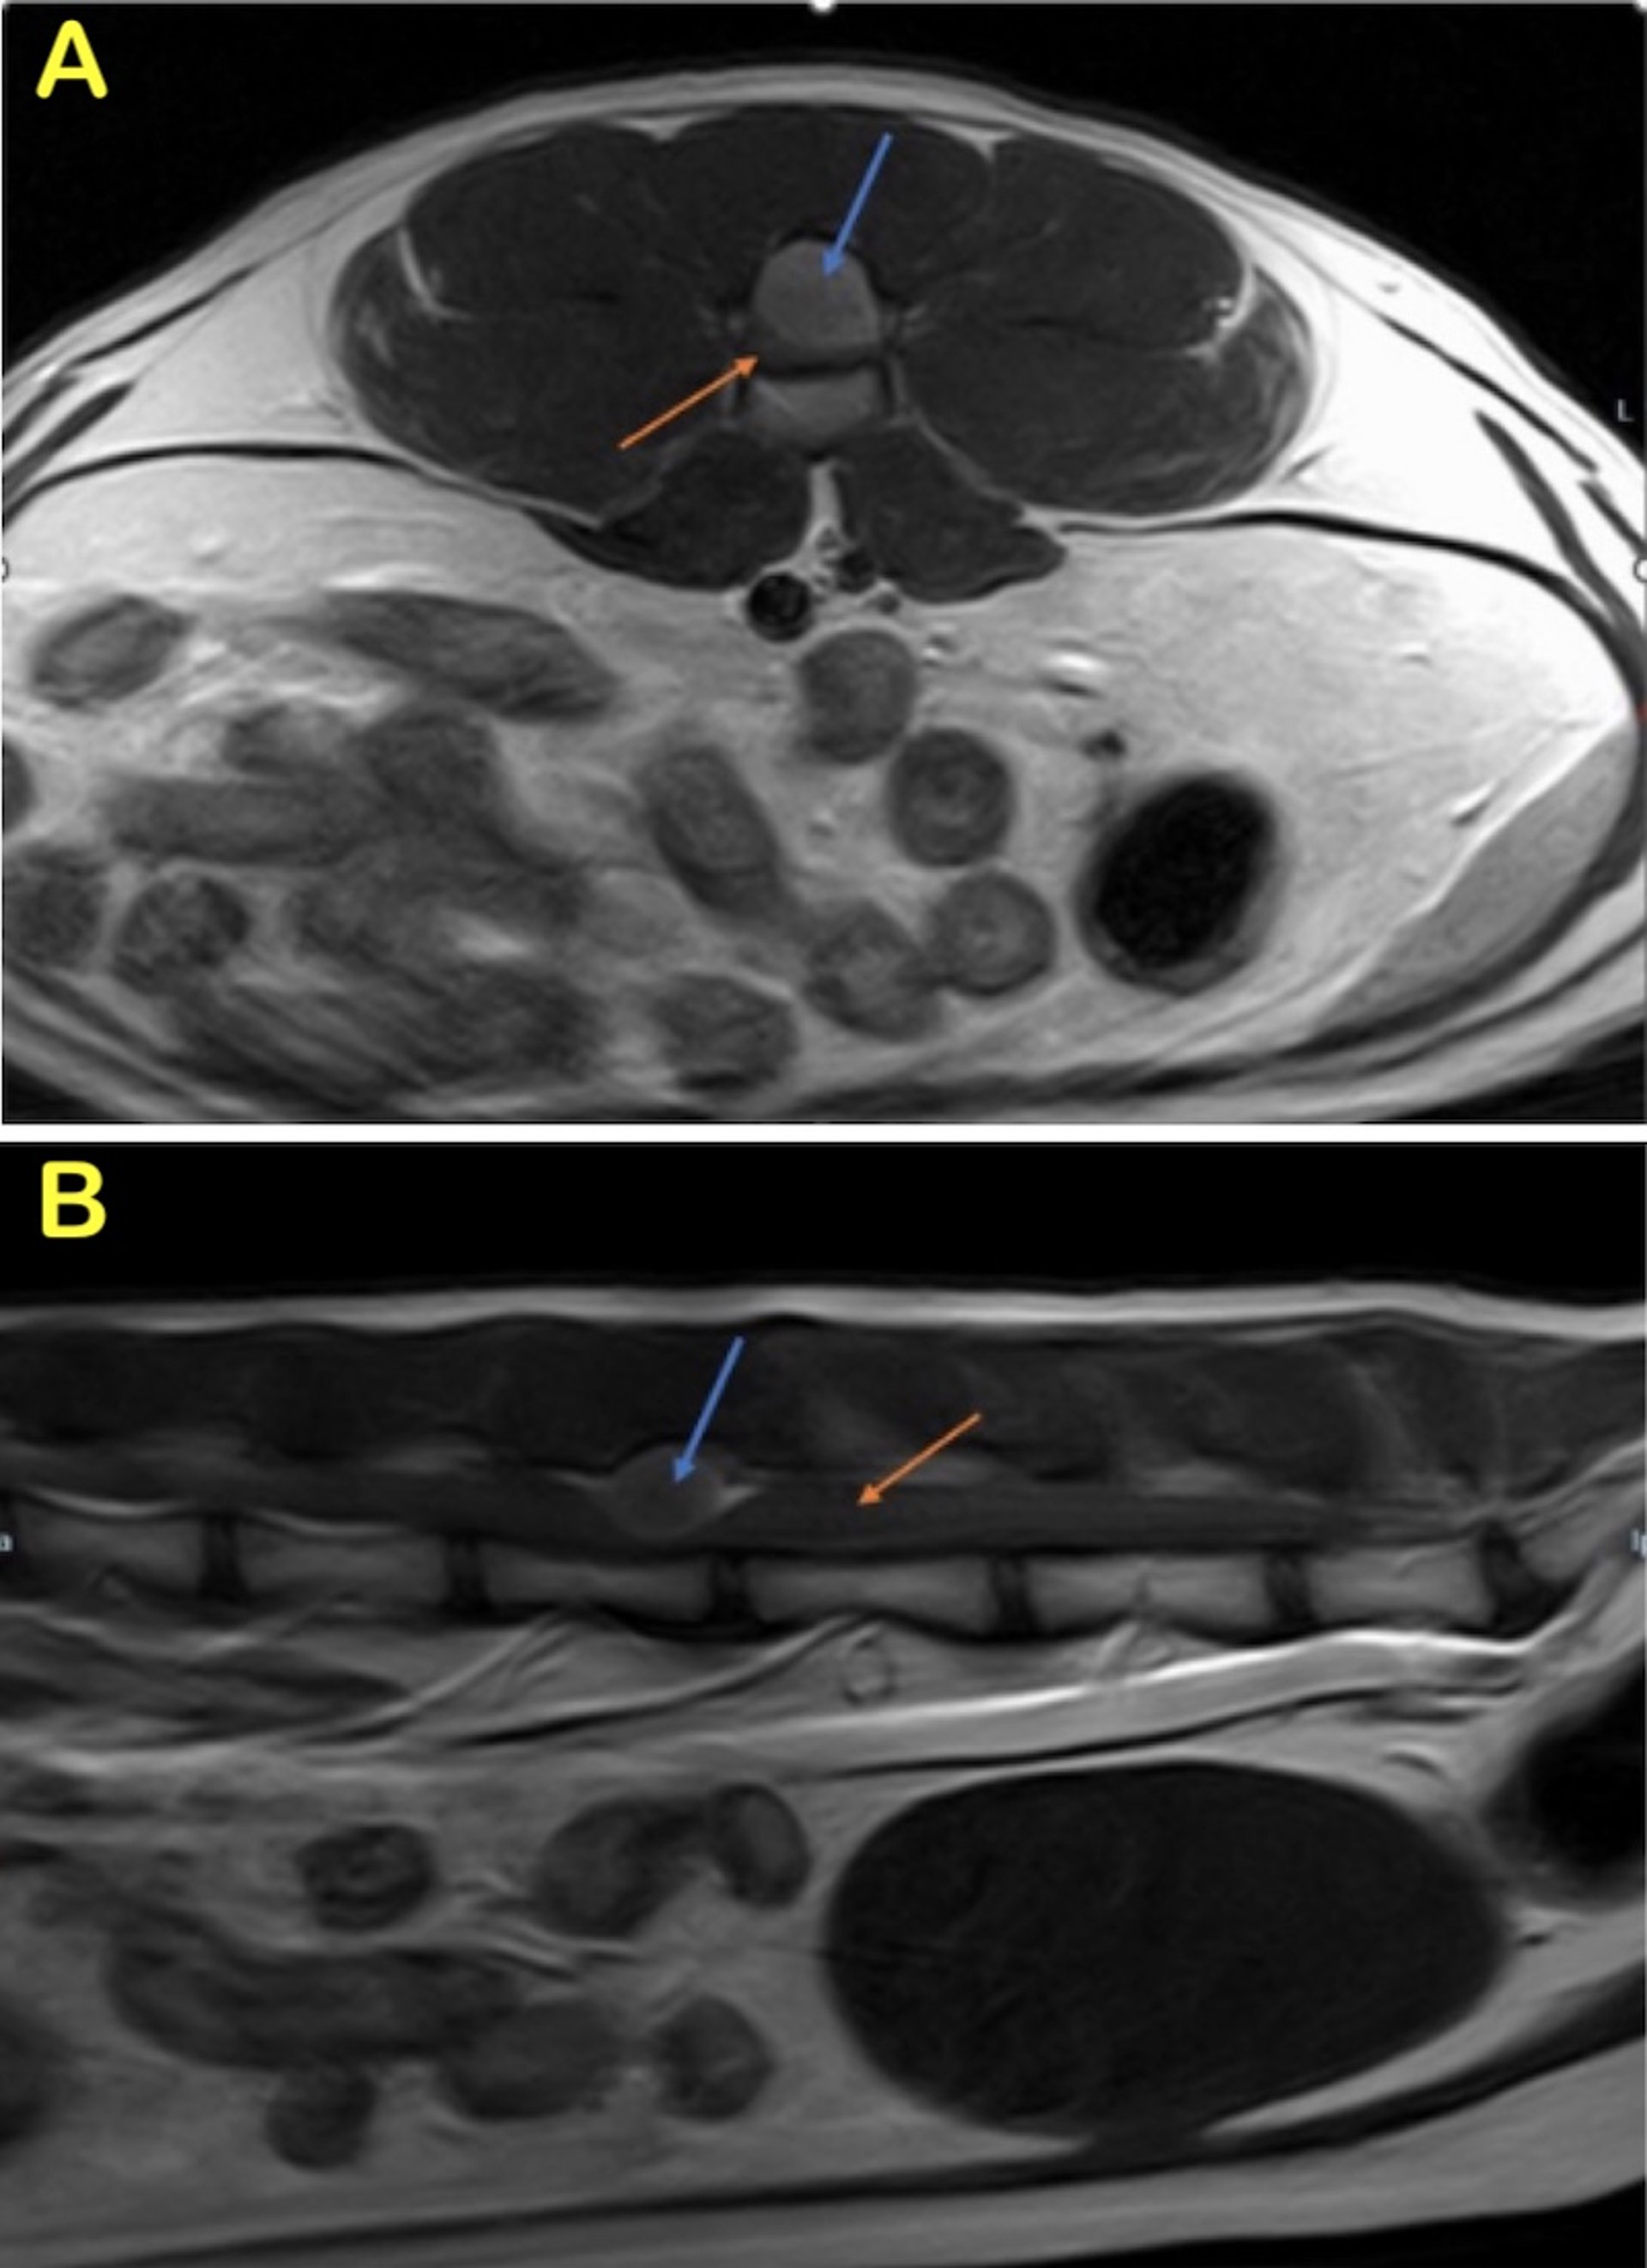

Spinal meningioma, MRI, cat

T1W postcontrast lumbar spine images of a spinal meningioma in a 13-year-old cat that showed difficulty walking for 1 year. The images show a large, well-defined, strongly contrast-enhancing extradural mass at L4. The blue arrow points towards the tumor, and on the sagittal image (B), a dural tail is visible both cranial and caudal to the mass. The orange arrow points to the normal spinal cord. On the axial view (A), the severe spinal cord compression can be appreciated due to the very small amount of normal spinal cord visible.

Courtesy of Dr. Baye Williamson.